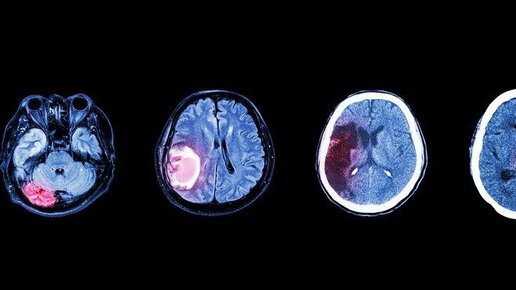

Менингиома головного мозга

Менингиома – серьезное заболевание, проявляющееся опухолевым образованием, возникающим из тканей головного мозга (арахноидального эндотелия). Болезнь, как правило, носит доброкачественный характер, медленно развивается и на протяжении длительного времени никак себя не проявляет. При этом новообразование может локализоваться в нескольких областях головного мозга, а порой возможна его трансформация в злокачественную опухоль. Что провоцирует развитие менингиомы, как она проявляется и какие методы лечения...